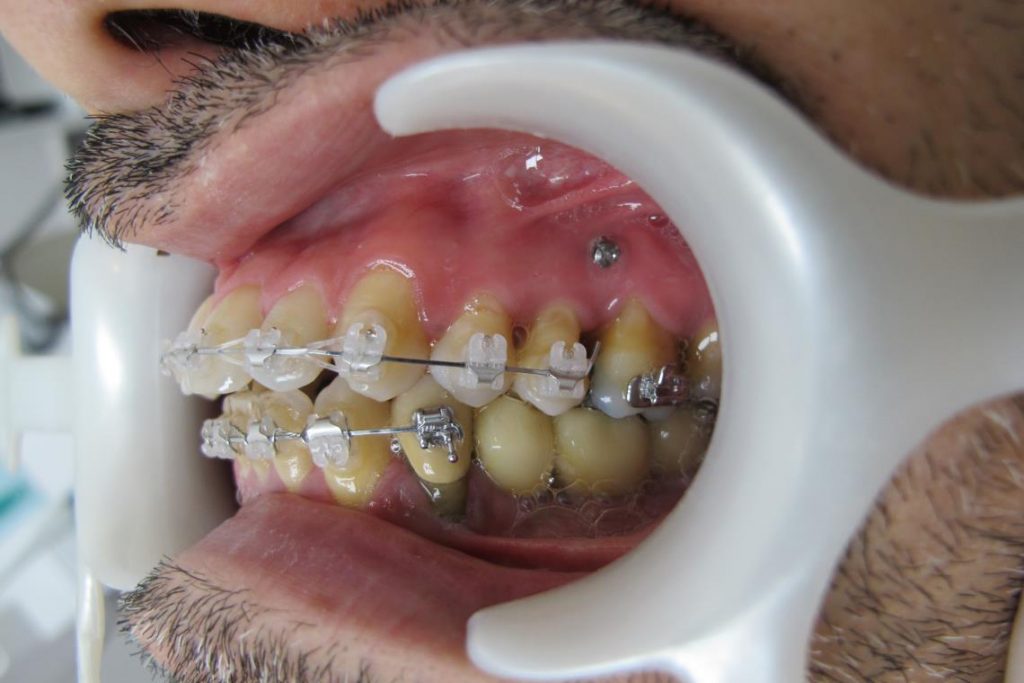

L’orthodontie vestibulaire esthétique

Un appareil multi-attache céramique est mis en place sur l’ensemble des dents.

L’utilisation d’attaches auto-ligaturantes en céramique n’entraine aucune coloration jaune inesthétique, ni aucun vieillissement dans le temps.

L’aspect des attaches reste donc inchangé tout au long du traitement.

Dans les cas de parodonte réduit où l’hygiène va être un élément déterminant, on préfère poser les attaches ( ou bagues) sur la face visible des dents c’est à dire en vestibulaire pour faciliter le passage de la brosse à dent et des brossettes avec un bon contrôle visuel.